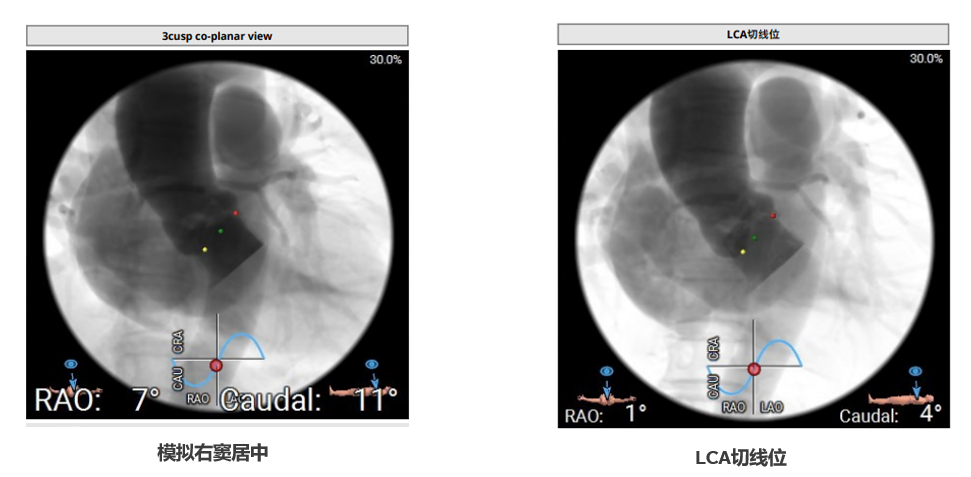

CUSP OVERLAP植入视图:

瓣膜定位和初始释放:采用美敦力标准化流程,应用Cusp overlap 技术,在模拟的左右窦重合的释放角度下将标记带调整到猪尾的中间开始释放

最后释放:转至三窦共面视角,调整LAO至瓣膜流入端无视差,再次评估确认后从无冠窦撤出猪尾导管,回拉导丝释放张力并做最后释放